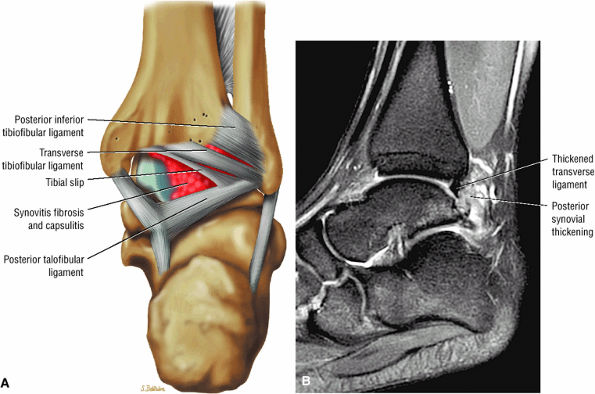

The syndesmotic ligaments consist of the anterior syndesmotic or anterior inferior tibiofibular ligament and the posterior syndesmotic or posterior inferior tibiofibular ligament, the interosseous membrane, and the transverse tibiofibular ligament.

The transverse tibiofibular ligament represents the posterior labrum of the ankle and projects inferior to the posterior tibial margin.

The tibial slip is the posterior intermalleolar ligament.